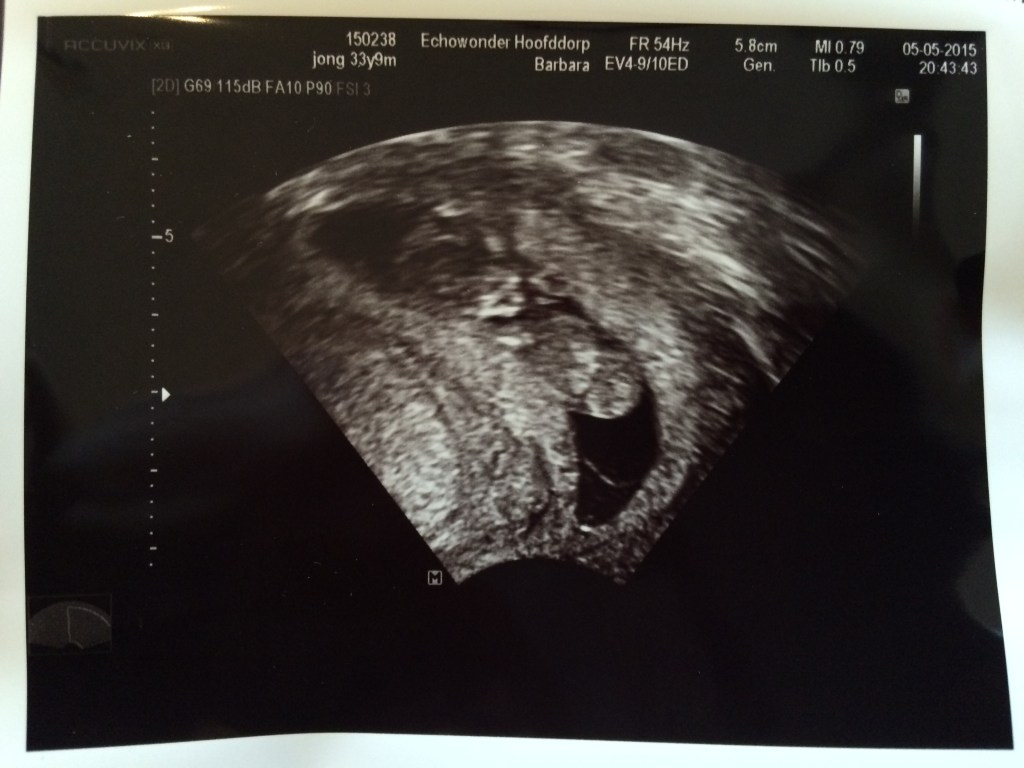

It took a while before I posted. Sorry about that but I became a mummy. I didn’t go to any gigs, I focused for the full 100% on my pregnancy.

We have a beautiful daughter called Roos (pronounce: Rose). She is born on November 19th 2015.

I found out I was pregnant after we came home from Cabo Verde in March.